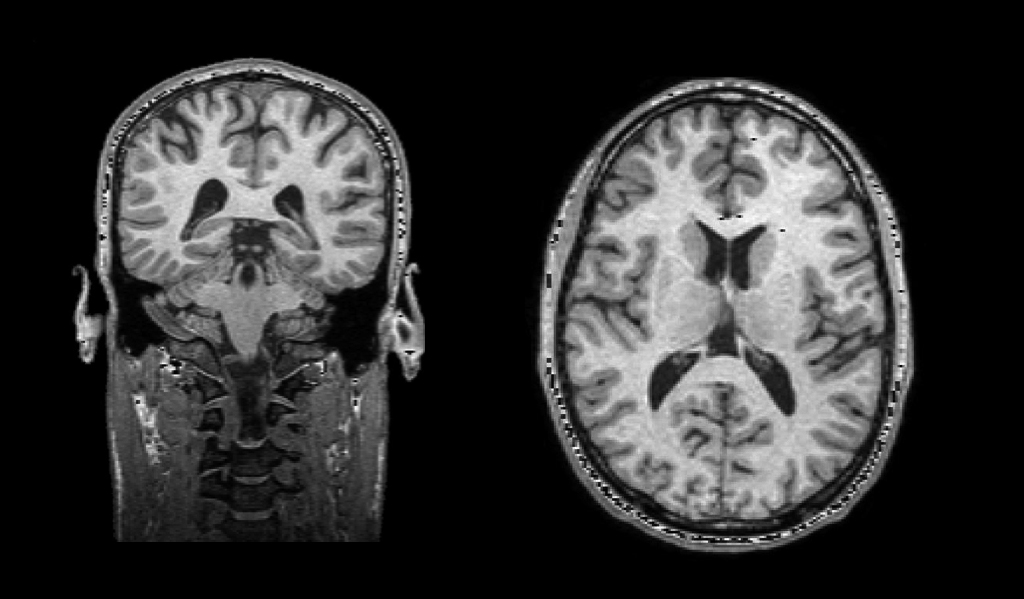

risonanza1

Sezioni coronale (sinistra) e sagittale (destra) della testa di un giovane maschio visualizzate da dati di risonanza magnetica nucleare.

Visto in sezione (qui in risonanza magnetica), il cervello mostra chiaramente la differenza tra quella che è stata chiamata materia grigia e la materia bianca, alla quale solo recentemente si comincia a dare la dovuta importanza.

La materia grigia è formata dai corpi cellulari e dai dendriti più corti e sottili, la materia bianca da quelli più lunghi, detti assoni, i cui fasci, anche fuori dal cervello, formano i nervi, e, all’interno del cervello, le connessioni tra le diverse regioni della corteccia.